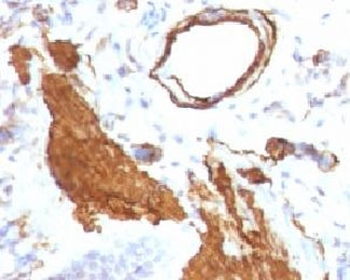

IHC: Formalin-fixed, paraffin-embedded Leiomyosarcoma stained with Smooth Muscle Actin antibody (clone SPM332).